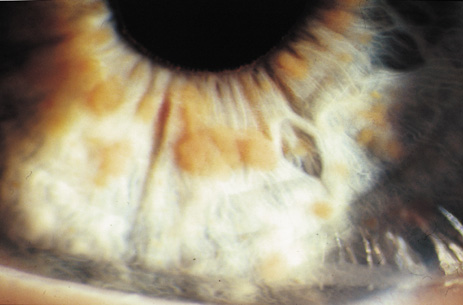

Lisch nodules are hamartomas (a tumor involving only those tissue elements normally found at the involved site) of the iris pigment epithelium. They are dome-shaped discrete lesions, are typically light brown in color, and may also be found in the angle.38 Lisch nodules appear earlier (33% at 2.5 years, 50% at 5 years of age)39 than neurofibromas. They are benign and can help to confirm diagnosis in children who may have café au lait spots as the only other clinical finding. Lisch nodules are present in nearly all adults with NF139,40 but are rare in NF2 (Fig. 3).41,42 Diffuse nodular iris nevi (also known as iris mamillations) should not be confused with Lisch nodules. Its clinical significance is not well established.43,44

Fig. 3. Neurofibromatosis type 1: Lisch nodules. These are hamartomas of the iris pigment epithelium. Lisch nodules are present in nearly all adults with NF1,39,40 but are rare in NF2.41,42

2. At least two Lisch nodules (Fig. 3)

Retinal hamartomas affect about 10% to 20% of patients (8% in one study91and 22% in another98) and may be associated with a more severe phenotype of NF2.91,98 Combined pigment epithelial and retinal hamartomas (CPERH) and epiretinal membranes have been reported.101–103 Lisch nodules are rare in NF2. The absence of Lisch nodules, in association with the presence of posterior subcapsular or cortical cataracts (Fig. 8) may aid the differentiation of NF1 and NF2.97,104,105 Optic nerve sheath meningiomas may cause significant visual impairment in the first years of life (Table 2).84,106

Fig. 8. Neurofibromatosis type 2: cortical wedge cataract. Lens opacities (cortical wedge and posterior subcapsular cataract) may be the initial manifestation of disease in 10%.98